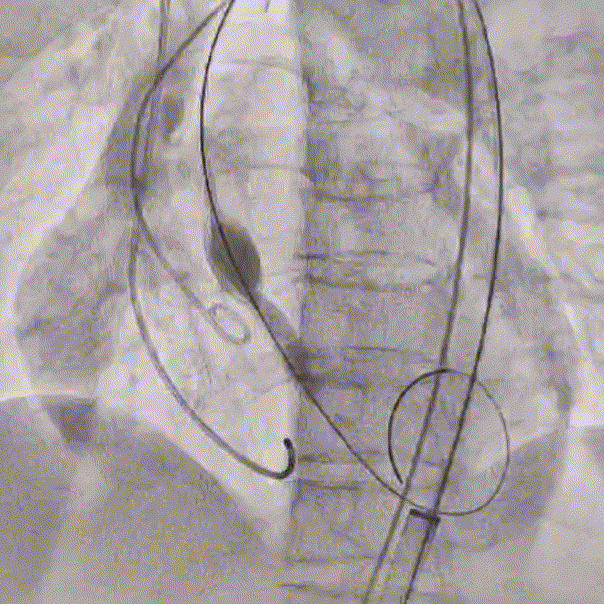

输送器顺畅过弓及跨瓣

瓣膜一次稳定释放